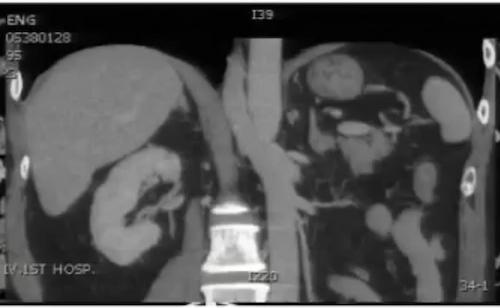

图10:中腹部增强CT显示腹主动脉前后各走行一左肾静脉,分别汇入下腔静脉

环主动脉型左肾静脉:左肾静脉主干出肾门后分成前、 后两支,前支走行正常,后支可在同水平或斜向右下走行,经过腹主动脉后方汇入下腔静脉,另有少见两条左肾静脉独立自肾门发出。主动脉后左肾静脉主干或分支受压,近端增粗,其属支包括左侧生殖静脉、肾上腺静脉及腰静脉曲张。

完全性主动脉后型左肾静脉:左肾静脉主干出肾门后横行走行,经过腹主动脉后方汇入下腔静脉,少数左肾静脉向右下走行,横行经过左髂总动脉后方汇入左髂总静脉。